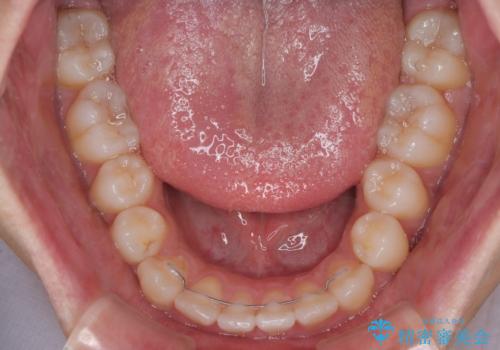

- 1年2ヶ月

- 「上下の前歯がガタガタしているのが気になる」とのことで来院された患者様です。

上下顎前歯部に叢生(歯の重なり・ガタつき)を認め、見た目だけでなく、歯磨きのしにくさも気にされて来院されました。